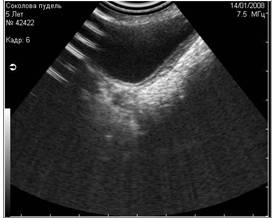

- вызванные недостаточным количеством УЗИ-геля, нанесённого на кожу (Рис.4) ;

Рис 4. Недостаточное количество геля при проведении УЗИ (правая половина снимка). |